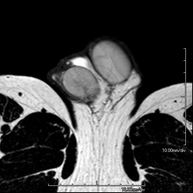

- Orbit MRI

This non-invasive diagnostic procedure uses an electromagnetic field and radio waves (from a transmitter and receiver) to acquire high-definition anatomical images of the orbits. It is a radiation-free procedure. Indicated for: double vision, trauma, suspected tumour, hyperthyroidism.